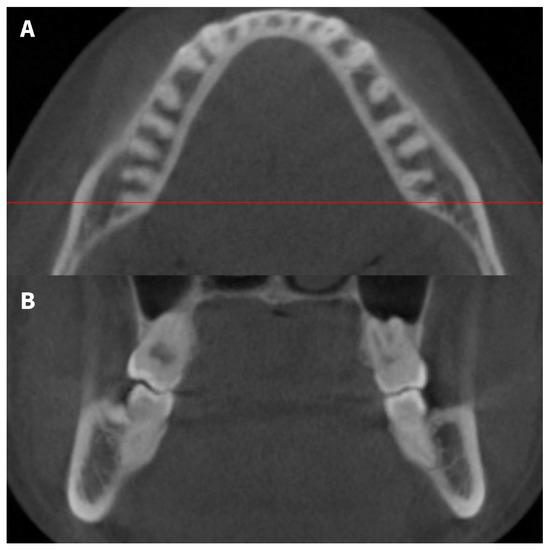

Figure 3.

(A) The distance between the root and the lingual cortical bone was measured in a plane parallel to the mandibular occlusal plane and 1, 3, and 5 mm away from the apex. (B) Schematic diagram showing the distance measured between the root and lingual cortical bone on the axial plane. (a) distance between molar roots and outer lingual cortical bone, (b) distance between molar roots and inner lingual cortical bone.

Measurements were made 1, 3, and 5 mm above the individual apex of the mesial and distal roots of the mandibular molars. In molars having two distal roots, the distance was measured at the distolingual root. In the C-shaped roots, the distance from the most protruding point of the mesial and distal parts was recorded.

If the roots invaded the lingual cortical bone, the distance between the roots and medial cortical bone was recorded as 0, even though periodontal ligament space was observed between the roots and lingual cortical bone.

Additionally, contact between the first and second molar roots and lingual cortical bone was assessed. If contact between molar roots and lingual cortical bone in the horizontal plane was suspected, the contact was confirmed in multiplanar reconstruction images (Figure 4).